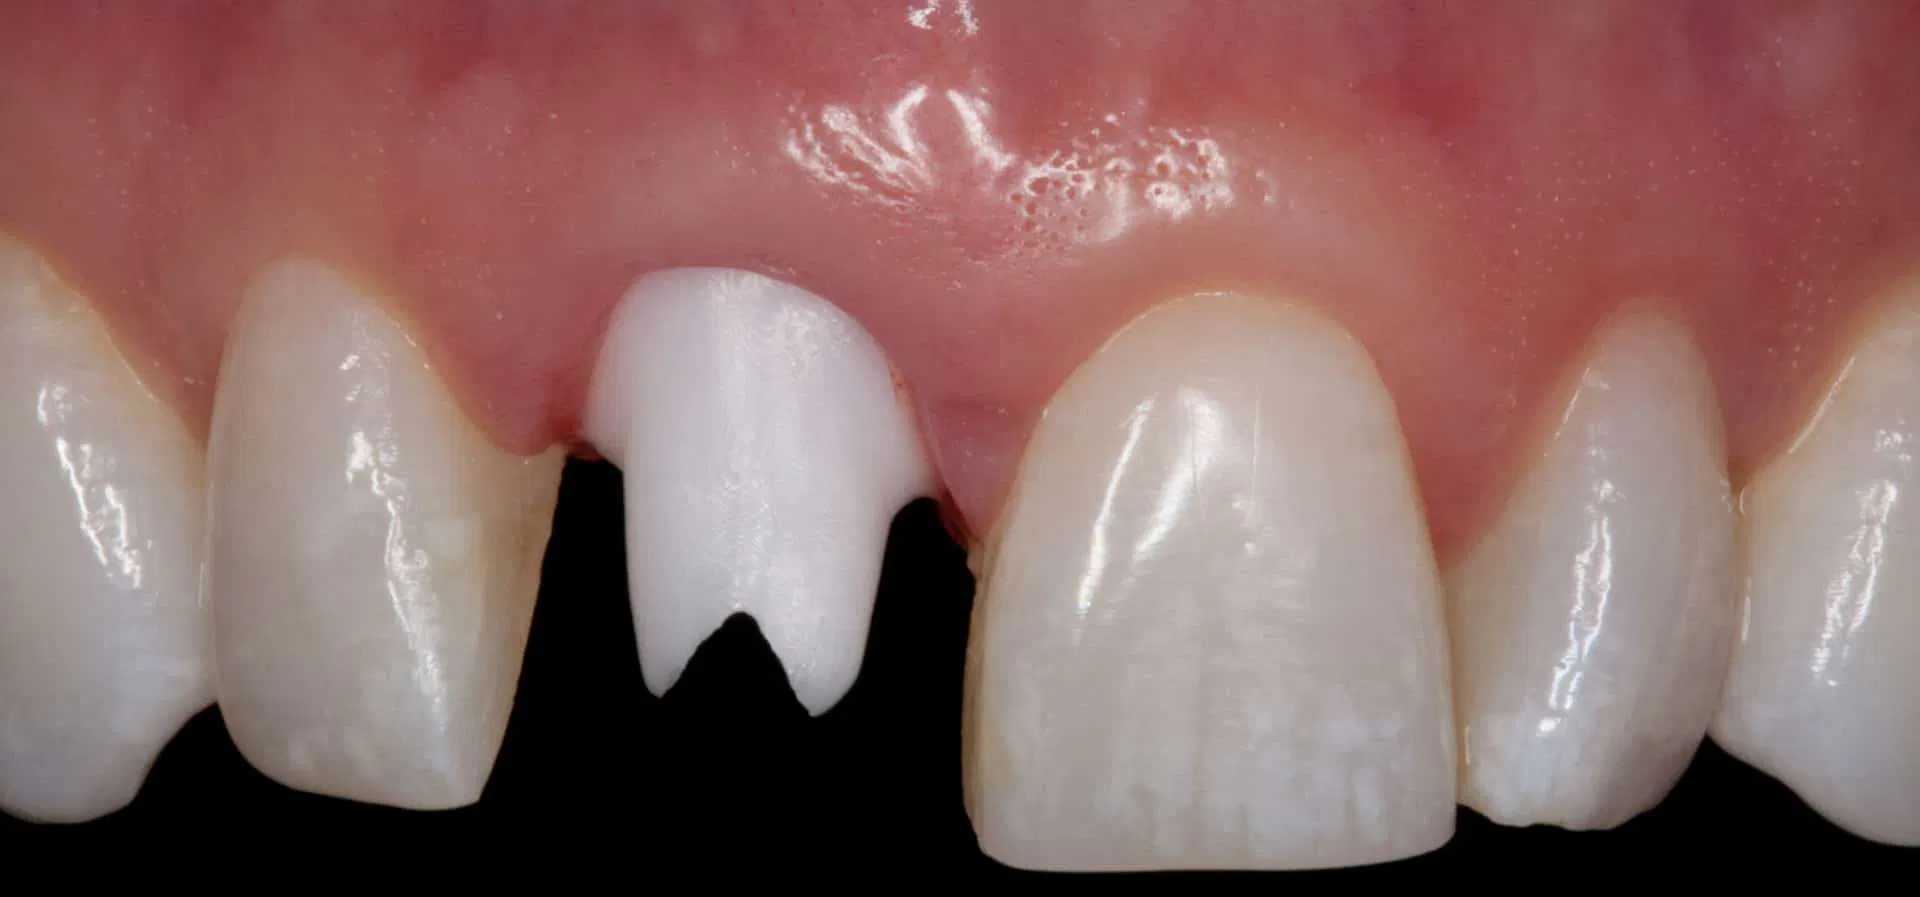

Before:Â Fractured/failed heavily treated upper right central incisor (tooth #8). The root is non-restorable and requires removal. The treatment of choice is a single implant supported restoration.

After: Single, all-ceramic crown attached to an all-ceramic, CAD-CAM designed and generated abutment (implant post). A delayed treatment approach was undertaken: tooth/root removal and grafting; 4 months healing; interim removable partial tooth replacement; implant placement; 6 months healing; proto-type (transitional fixed) implant crown, then the definitive implant restoration. The new tooth blends in perfectly with the natural, adjacent teeth.